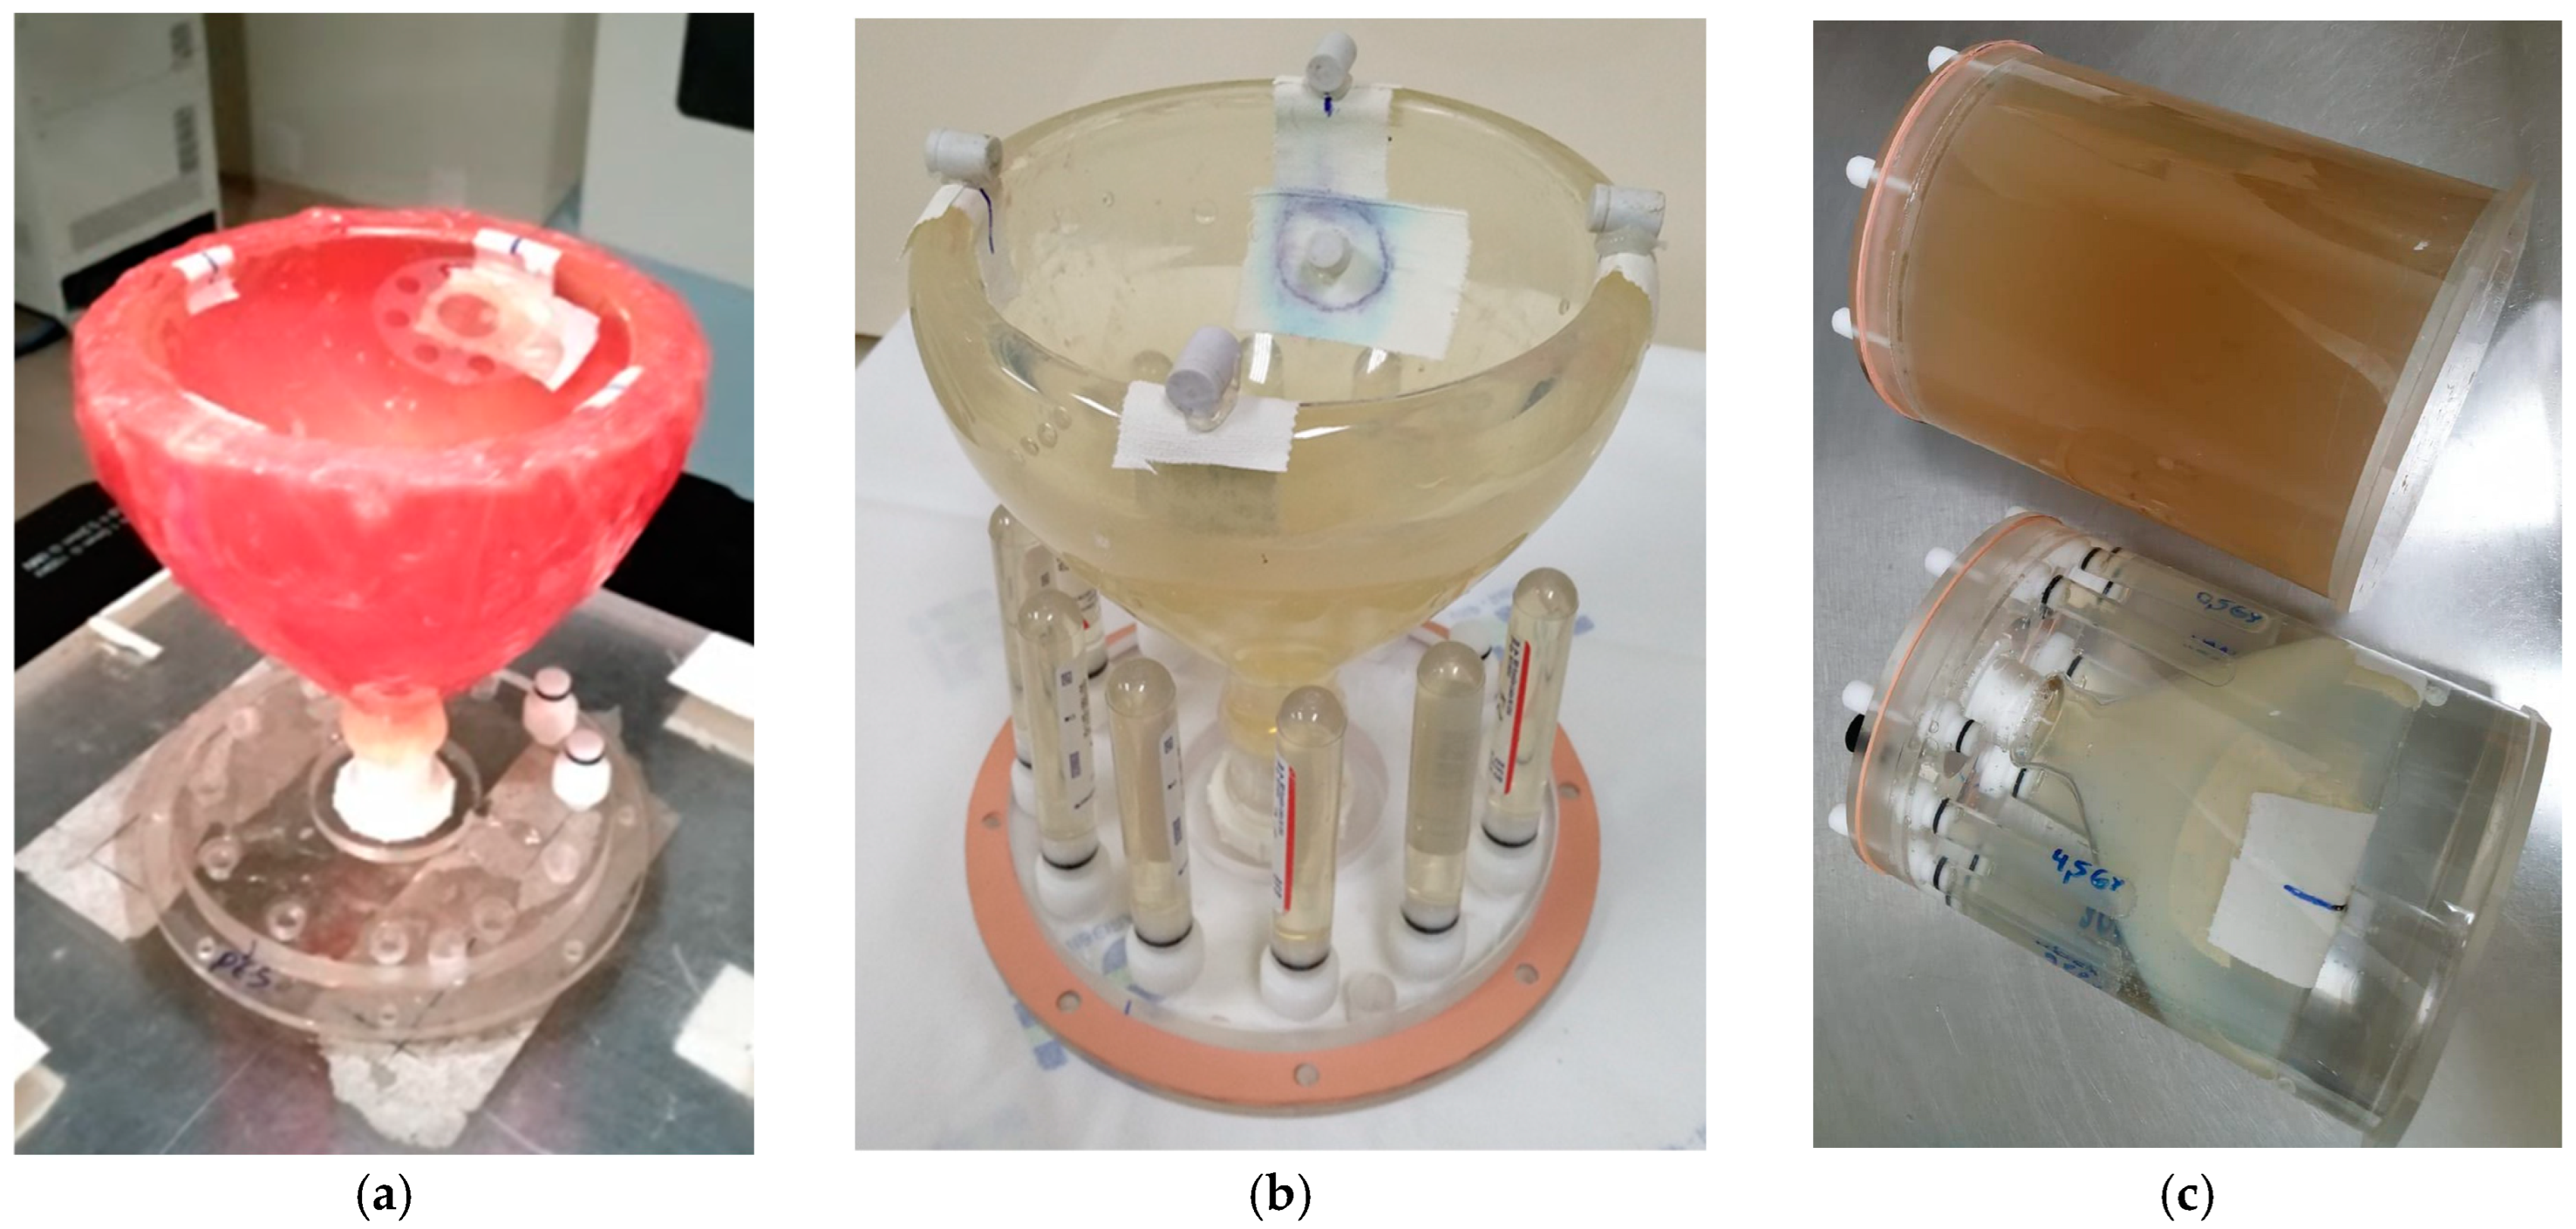

4. Materials and Methods